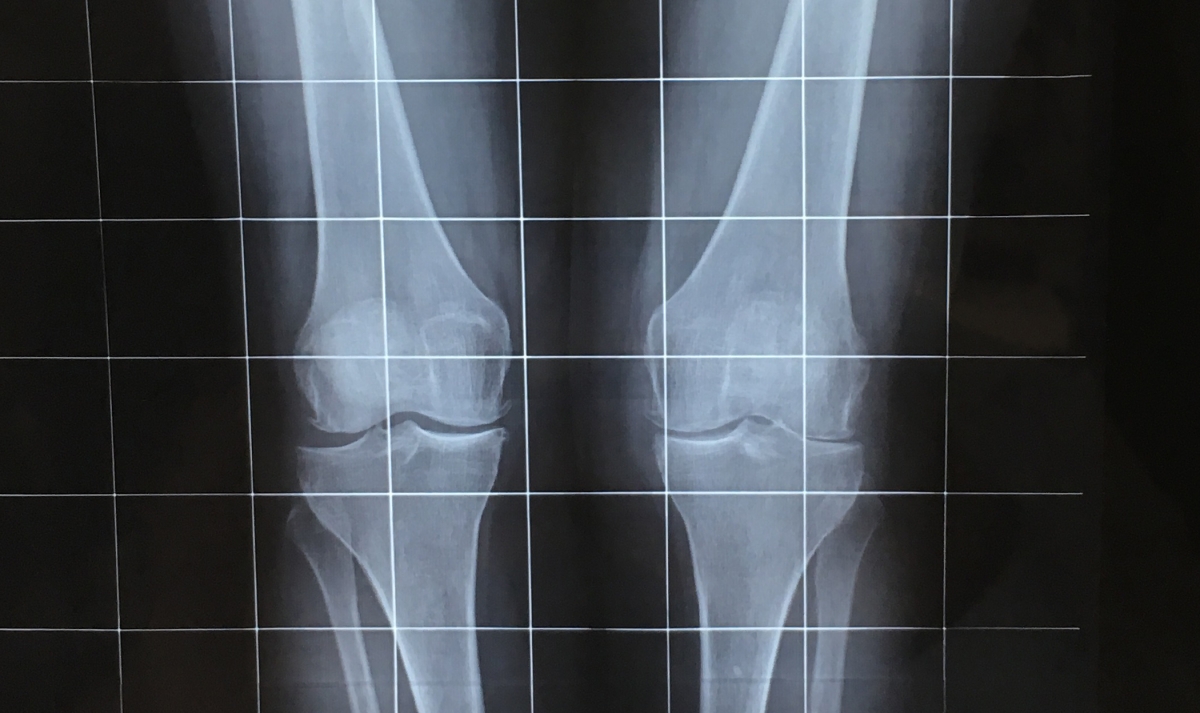

Se sospecha que hay una degeneración articular y de disimetría de miembros inferiores, por lo que se solicita una radio telemetría. Tras la prueba no se aprecia una asimetría muy fuerte en cuanto a longitud de las piernas, por lo que de inicio no se opta por tratar la disimetría.

En la radiografía se puede apreciar como la rodilla derecha tiene menos espacio articular en la zona externa, debido a la degeneración tanto del menisco como del cartílago.